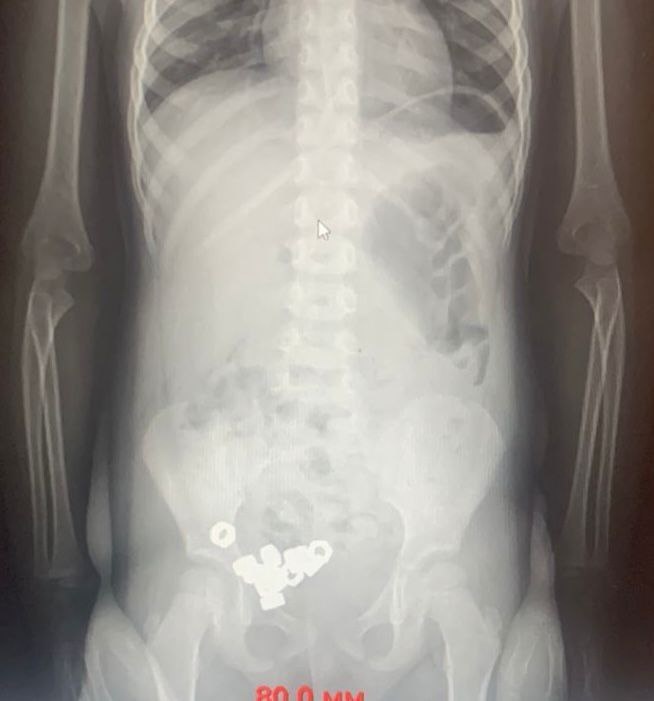

Трехлетний малыш проглотил 16 гаек в Воронеже. Родители привезли мальчика в больницу с предположением, что он проглотил инородные тела. При этом какие-либо симптомы у ребенка отсутствовали. Врачи провели рентген брюшной полости. Тот показал наличие 16 маленьких гаек в ЖКТ мальчика. Медики выбрали консервативную тактику решения его проблемы. Ребенку назначили диету, покой, контроль стула и рентгенографию в динамике. На третий день гайки вышли естественным путем, а малыша выписали. Гайки были настолько вкусными? #Воронеж 🇷🇺 В Стране. Подписаться

Врачи провели рентген брюшной полости. Тот показал наличие 16 маленьких гаек в ЖКТ мальчика. Медики выбрали консервативную тактику решения его проблемы. Ребенку назначили диету, покой, контроль стула и рентгенографию в динамике. На третий день гайки вышли естественным путем, а малыша выписали.